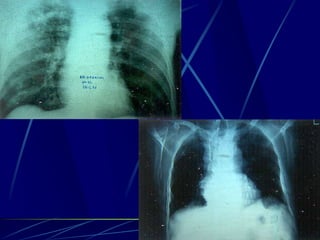

Φυματίωση της σπονδυλικής στήλης